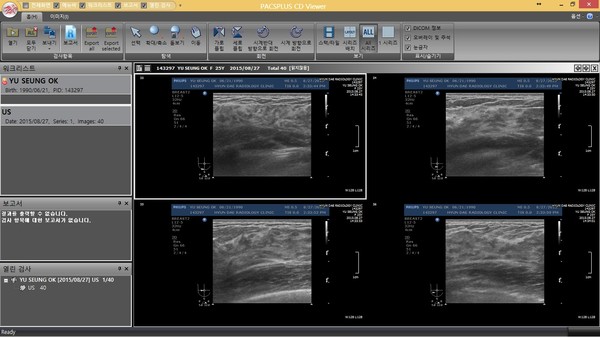

모델 유승옥이 가슴성형 논란에 휩싸였다.우월한 몸매로 주목받은 유승옥은 동양인으로는 가지기 힘든 신체사이즈와 몸매 비율을 보이며 여성들의 부러움과 함께 항상 성형수술 논란을 받아 왔다.이에 유승옥은 여러 방송을 통해 가슴수술 질의에 대해서는 줄 곳 하지 않음을 주장하였다.지난 24일 방영된 MBC ‘다큐스페셜-머슬녀 전성시대’ 유승옥 출연 분량 중 겨드랑이 부근의 블랙탄이 마치 가슴수술 후 발생하는 흉터와 흡사해 보이는 장면이 전파를 타, 실시간 검색어에 오름과 함께 온라인 커뮤니티, 댓글 등을 통해 가슴성형 논란이 다시금 불거졌다.이에 유승옥 소속사 프로페셔널 엔터테인먼트 측은 “이번 MBC 다큐멘터리 문제의 화면 방영 이 후 지난 유승옥의 발언은 모두 거짓처럼 퇴색 되었으며, 유승옥의 노력을 장점으로 판단하여 인연이 되었던 여러 관련주 분들이 난색을 표하며 진실규명을 요구 하는 등의 문제가 발생되고 있다.” 며 “이에 관련된 논란 잠식을 위해 모 외과에서 X-RAY와 CT 촬영을 진행하여 보형물 미 삽입에 대한 진단을 받았다.” 며 함께 자료를 공개하였다.또한 유승옥 기획사 프로페셔널 엔터테인먼트 관계자는 “다큐스페셜 촬영 진행 중 촬영팀이 미리 답변을 정해놓고 유도 질문하는 것, 조명조차 준비되지 않은 지하 스튜디오 촬영 환경 상 좋지 않은 결과를 초래할 것을 우려, 제작팀과의 합의하에 촬영을 중단하고 해당 촬영 분은 방영되지 않는 내용을 쌍방 합의간에 결정하였다.”이어 “하지만 8월 24일 사측과의 동의 없이 무단으로 방송을 강행하였고 해당 방송 본에는 비키니 착장 영상과 더불어 스튜디오 운동영상이 전파를 타게 되었다.” 며 난색을 표명함과 함께 사전 동의 없이 방송을 강행한 MBC 다큐스페셜 측에 유감을 표명하였다.